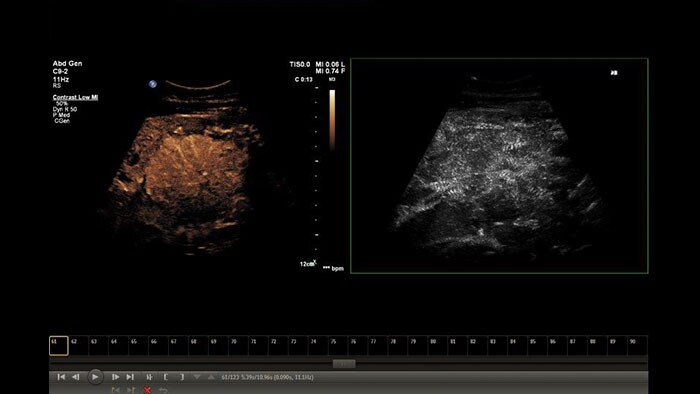

US Q-App MicroVascular Imaging (MVI)

Enhanced vessel conspicuity

US Q-App Microvascular Imaging (MVI) supports you in mapping contrast agent progression with contrast enhanced ultrasound (CEUS) for tumor assessment and monitoring.

Benefits

- Review loops from Philips EPIQ and iU22 systems including side-by-side files.

- Motion compensation algorithm selectable in preferences menu.

- Append to patient exam.

- Compatible with Philips EPIQ, Affiniti , iU22 CX50, and HD15 systems.